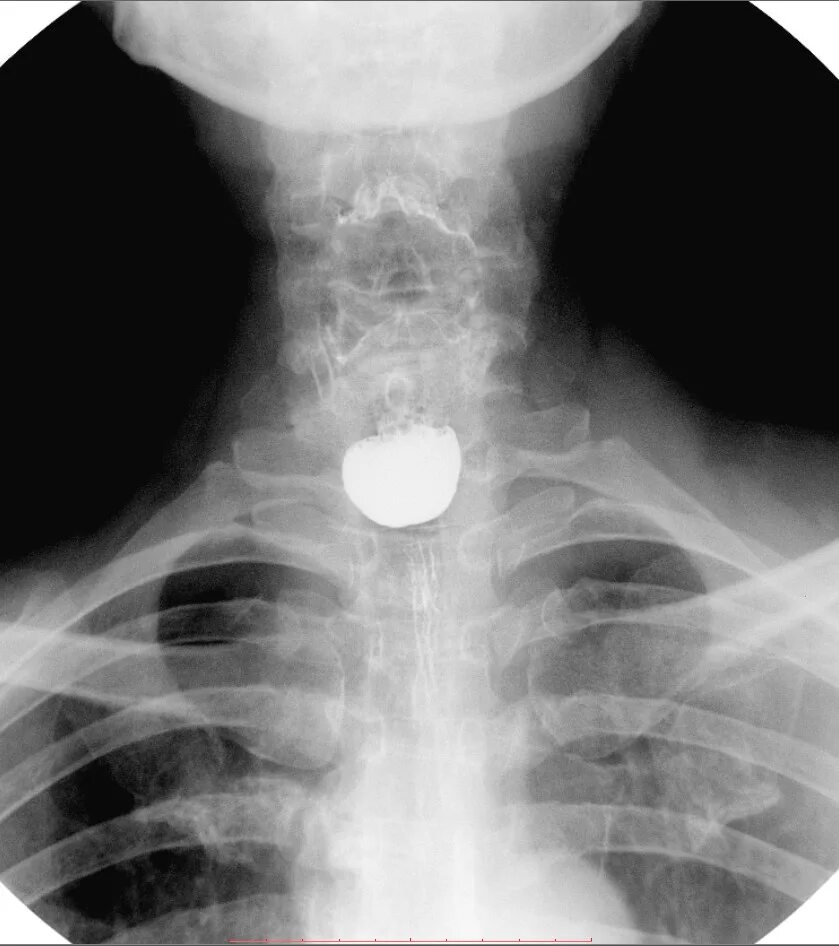

Дивертикул трахеи